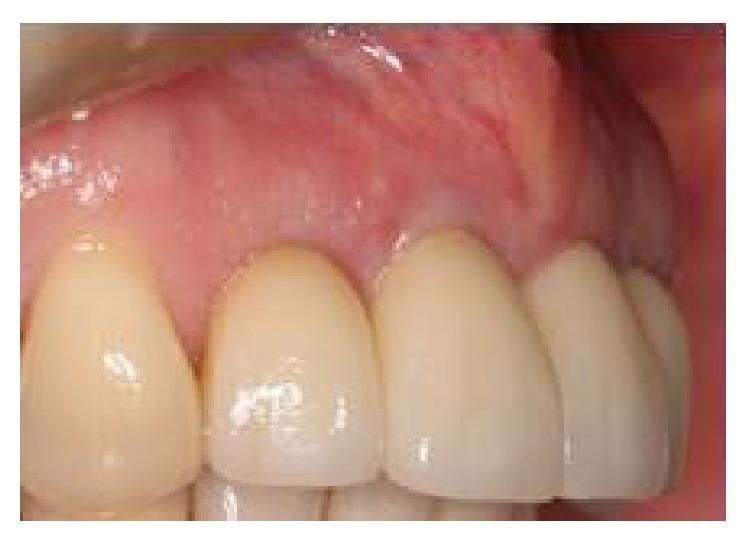

The functional and aesthetic restoration of teeth compromised due to aggressive periodontitis presents numerous challenges for the clinician. Horizontal bone loss and soft tissue destruction resulting from periodontitis can impede implant placement and the regeneration of an aesthetically pleasing gingival smile line, often requiring bone augmentation and mucogingival surgery, respectively. Conservative approaches to the treatment of aggressive periodontitis (i.e., treatments that use minimally invasive tools and techniques) have been purported to yield positive outcomes. Here, we report on the treatment and five-year follow-up of patient suffering from aggressive periodontitis using a minimally invasive surgical technique and implant system. By using the methods described herein, we were able to achieve the immediate aesthetic and functional restoration of the maxillary incisors in a case that would otherwise require bone augmentation and extensive mucogingival surgery. This technique represents a conservative and efficacious alternative to the aesthetic and functional replacement of teeth compromised due to aggressive periodontitis.

侵袭性牙周炎导致牙齿功能和美观受损,给临床医生带来诸多挑战。牙周炎引起的水平骨吸收和软组织破坏会妨碍种植体植入以及美观的牙龈微笑线的再生,通常分别需要进行骨增量和膜龈手术。据称,侵袭性牙周炎的保守治疗方法(即使用微创工具和技术的治疗方法)能产生积极效果。在此,我们报告了一名侵袭性牙周炎患者采用微创外科技术和种植系统的治疗及五年随访情况。通过使用本文所述方法,在原本需要骨增量和广泛膜龈手术的病例中,我们成功实现了上颌切牙的即刻美观和功能恢复。该技术是侵袭性牙周炎导致牙齿功能和美观受损时,一种保守且有效的替代治疗方法。